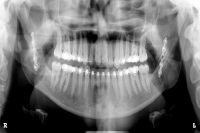

Oralchirurgie – Implantologie (zertifiziert)